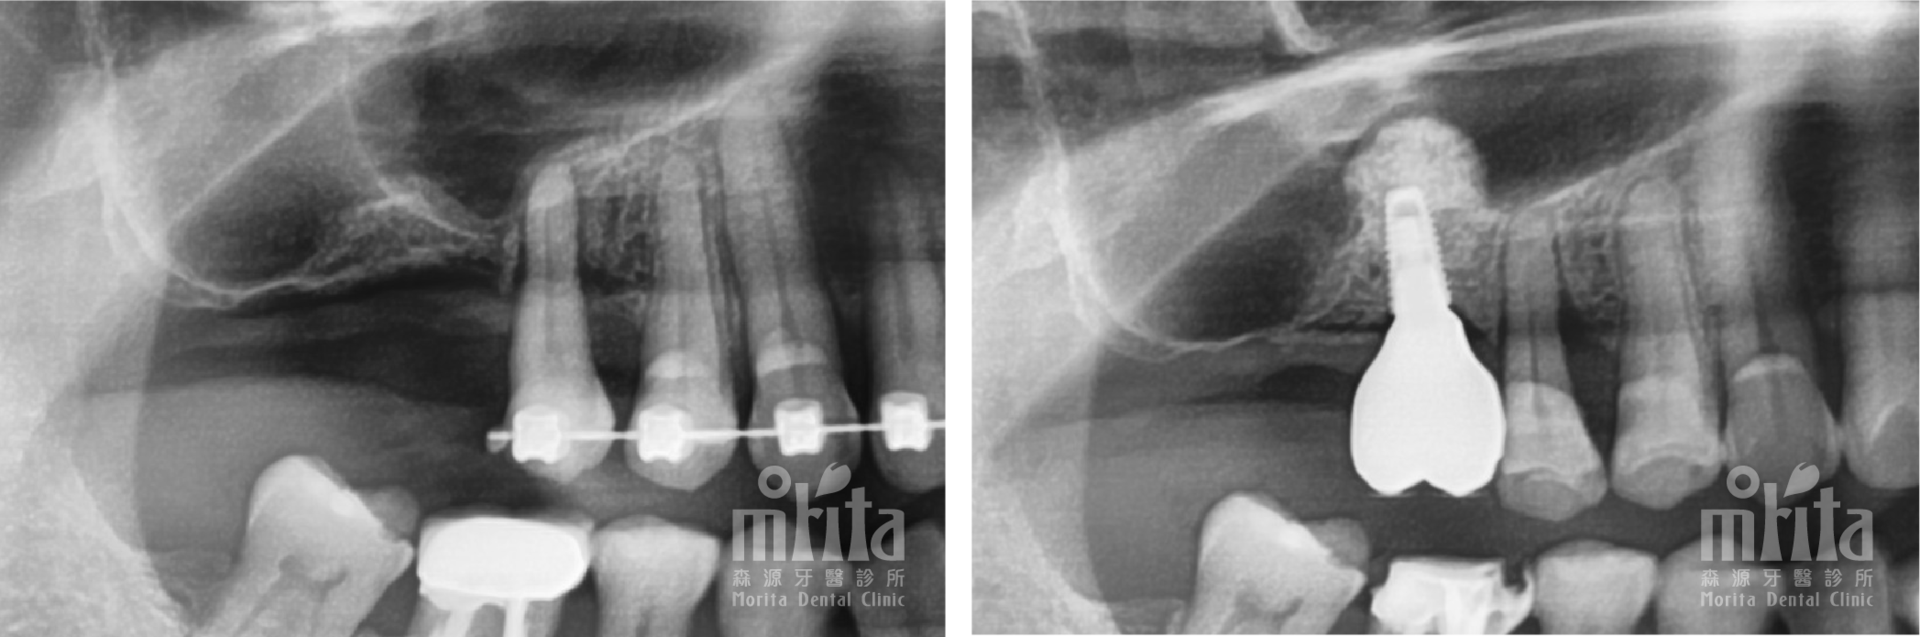

案例二:骨脊保存術 Ridge Preservation

案例二:骨脊保存術 X光片